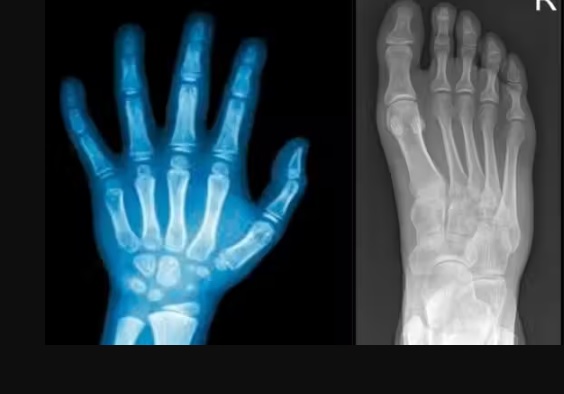

A cola que regenera ossos quebrados em apenas 3 minutos, criada na China, foi inspirada na aderência das ostras. – Fotos: Radiodonto/Medway

150 pessoas participaram dos testes clínicos, com resultados positivos em segurança e eficácia. Em um dos casos, uma fratura complexa de punho foi estabilizada em apenas três minutos com uma incisão de cerca de 2 a 3 centímetros, e após três meses o paciente recuperou a função sem complicações.

A cola para ossos quebrados pode ser usada em fraturas com múltiplos fragmentos até procedimentos ortopédicos e dentários, o que abre caminho para uma revolução nas cirurgias minimamente invasivas.